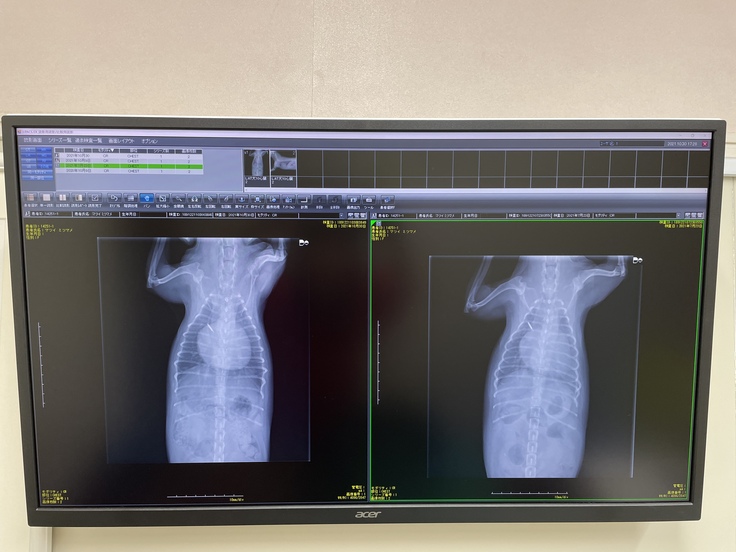

右が今年7月に、呼吸困難を起こした時の画像です。肺に水が既に浸潤して、心臓の輪郭がボヤけています。

右が昨年10月の画像、今年10月撮影。心肥大により気管が圧迫されています。